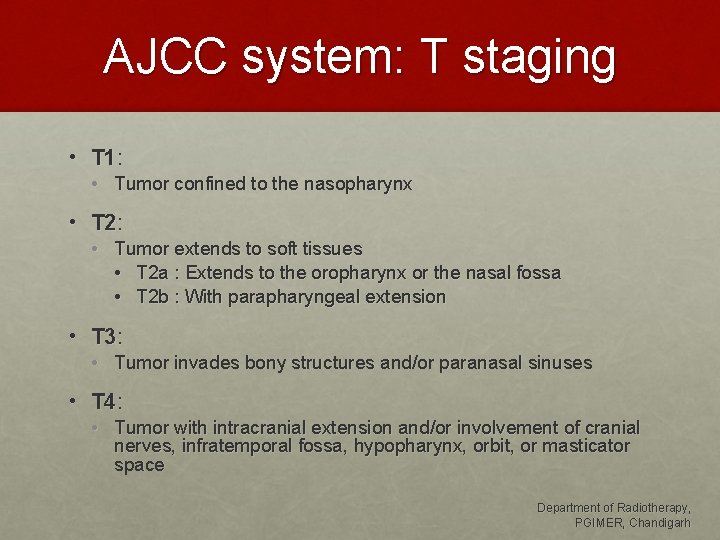

AJCC system: T staging • T 1: • Tumor confined to the nasopharynx • T 2: • Tumor extends to soft tissues • T 2 a : Extends to the oropharynx or the nasal fossa • T 2 b : With parapharyngeal extension • T 3: • Tumor invades bony structures and/or paranasal sinuses • T 4: • Tumor with intracranial extension and/or involvement of cranial nerves, infratemporal fossa, hypopharynx, orbit, or masticator space Department of Radiotherapy, PGIMER, Chandigarh